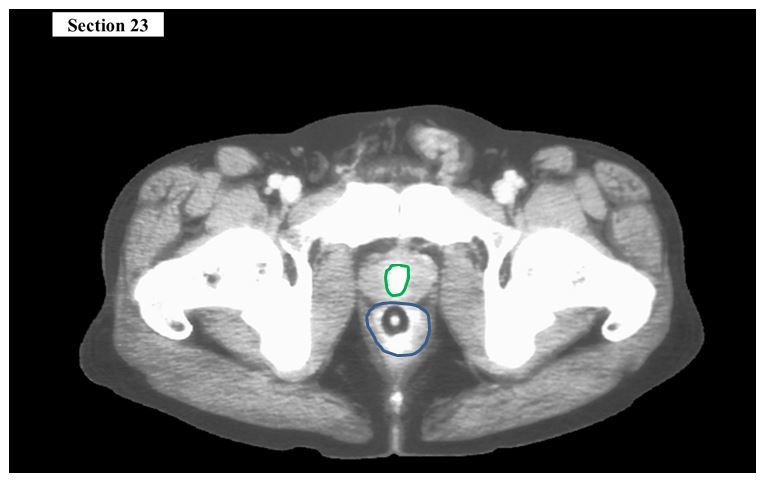

Q

The green structure is the ___

The blue organ is the ___

A

urethra

rectum